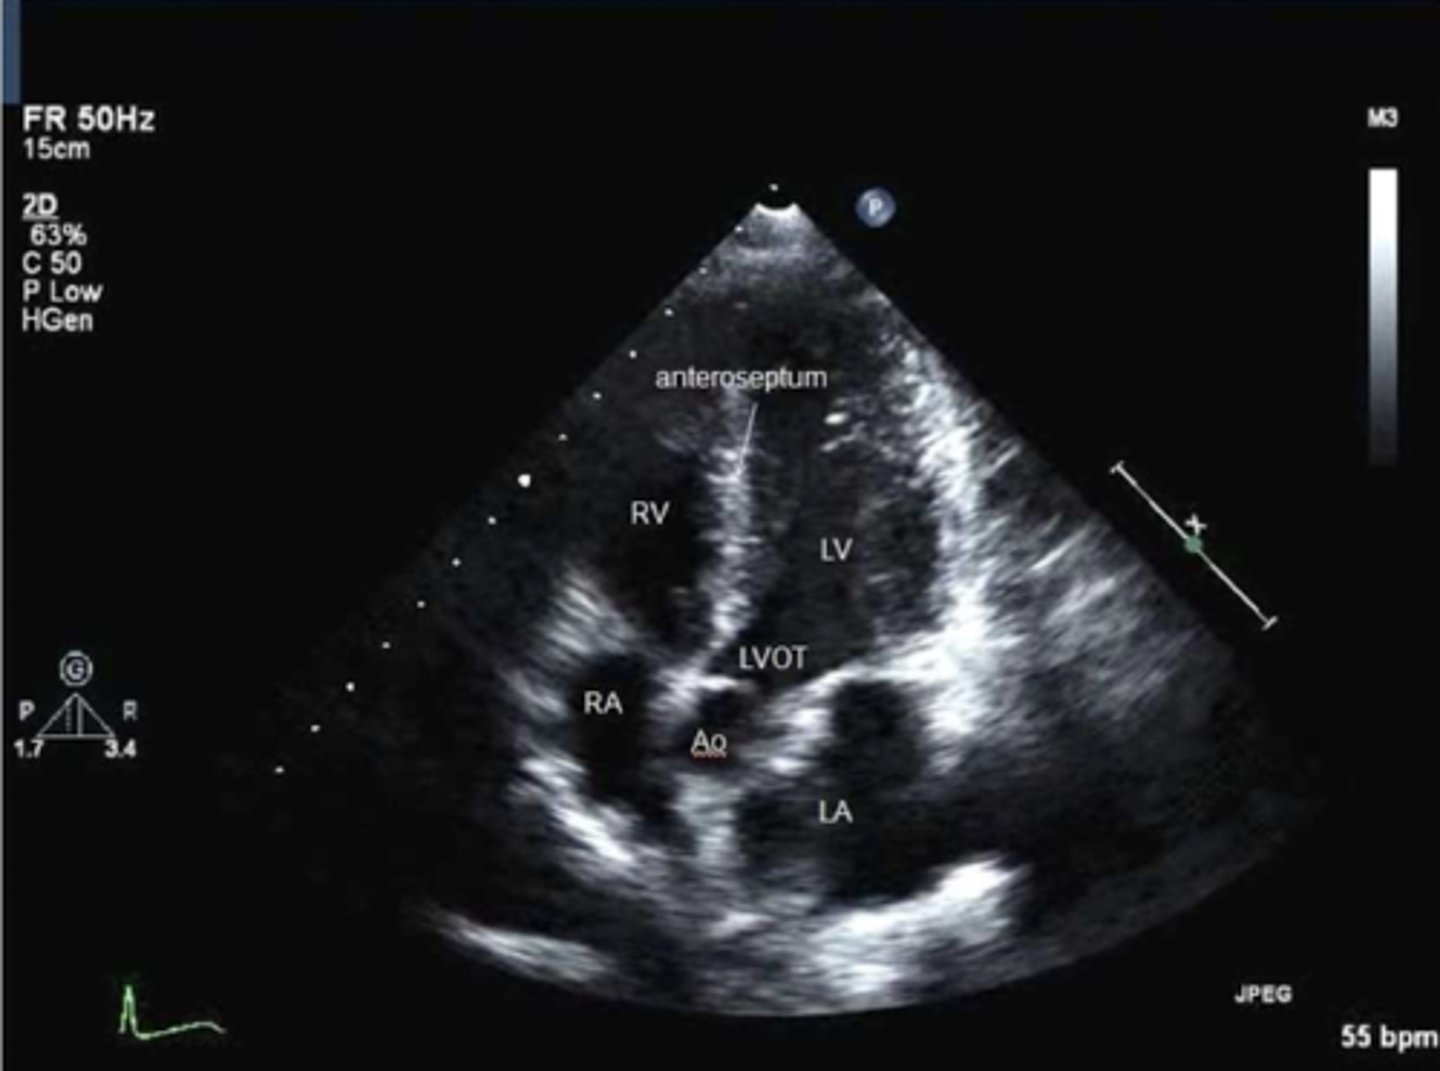

A5 is used to visualize ____, ____, and _____

TV, MV, and AoV